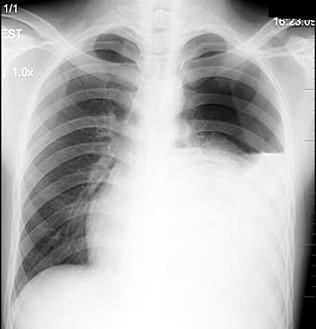

秒懂胸片!扒一扒胸片的基础知识

男,27岁,胸痛,胸片检查如图,最可能的诊断是()

[单项选择题]患者男性,18岁,感胸闷气逼,胸片检查见图,最合理的诊断是

秒懂胸片扒一扒胸片的基础知识

正常胸片图片图解

胸片正常图片

正常胸片图

正常胸片影像图片

正常胸片

胸片怎么看